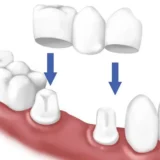

Bị mẻ răng khiến nụ cười của bạn kém thẩm mỹ, bạn mất tự tin trong các giao tiếp hàng ngày? Không những vậy, điều này còn